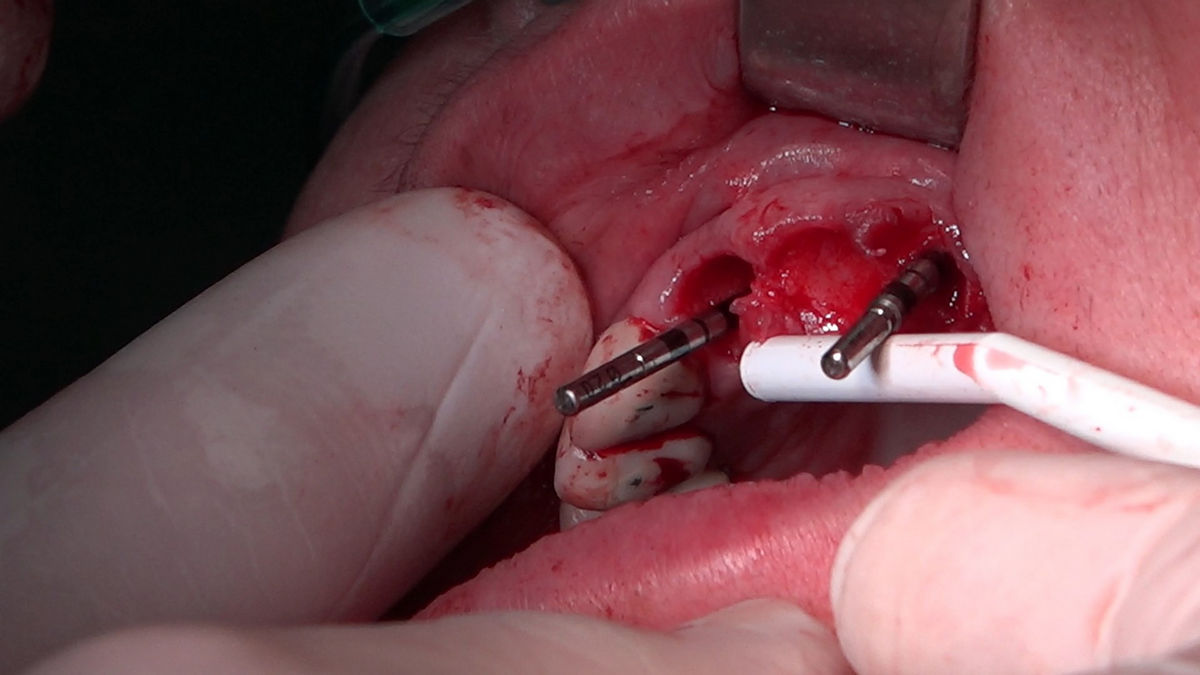

Chirurgia implantologiczna to temat wiodący 5 Sesji X Sezonu Practiculum Implantologii, która się odbyła 23-24 października 2020 roku. Bierze w nim udział 16 adeptów implantologii stomatologicznej. Zabiegi z udziałem Pacjentów jak zwykle poprzedziło omówienie i planowanie, tym bardziej, że zgodnie z planem wykonana została implantacja z wykorzystaniem szablonu chirurgicznego, który przygotowało laboratorium dentystyczne Wiligała Lab. Kursanci wykonywali szereg zabiegów implantologicznych i chirurgicznych oraz regeneracyjnych z zastosowaniem PRF, w tym sinus lift. Przeprowadzali je pod kierunkiem Lidera Umiejętności Implantologicznych dr n.med. Violetty Szycik, która wysoko oceniła wykonanie zabiegów.